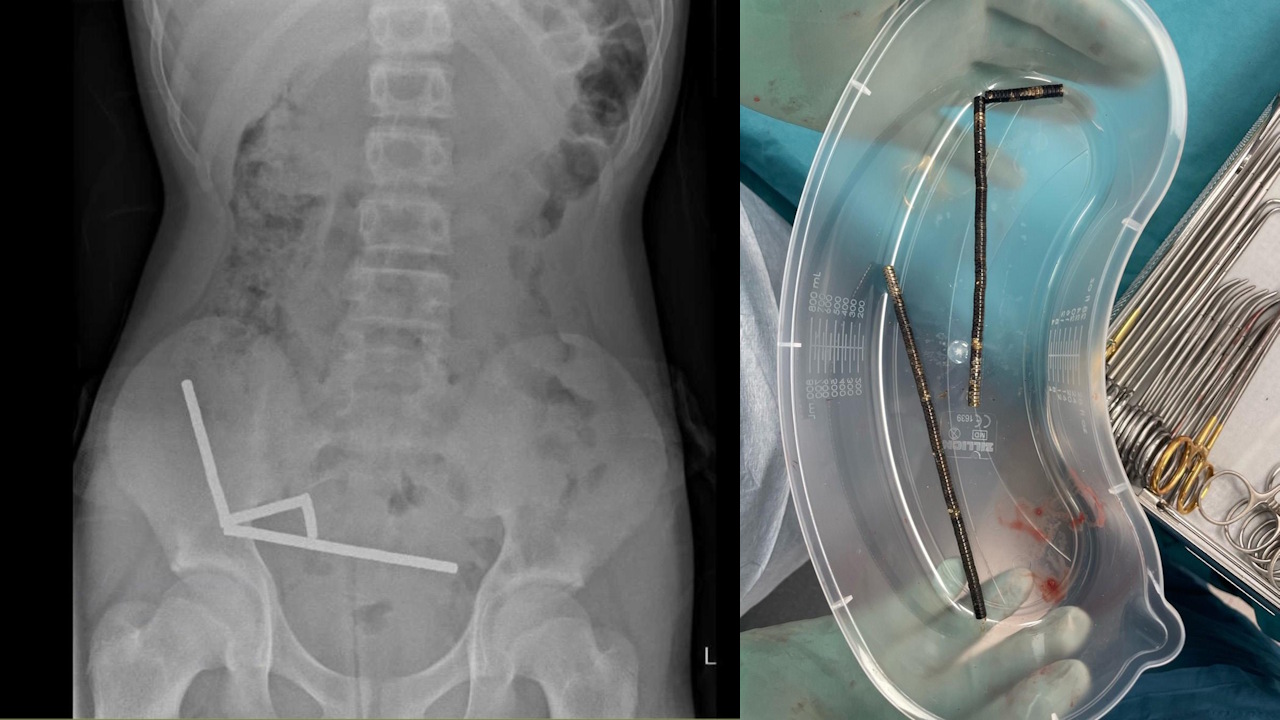

Чотири лінії з магнітів на рентгенівському знімку та після видалення з тіла пацієнта. Lekamalage et al. / New Zealand Medical Journal, 2025

Хлопець звернувся до лікарні за тиждень після того, як проковтнув магніти. На момент звернення він уже чотири дні страждав від болю в животі, а під час обстеження права нижня частина його живота була максимально чутливою. Рентген і комп’ютерна томографія живота показали, що 80-100 магнітів зібралися в чотири лінії в різних відділах кишківника та трималися разом завдяки силі магнітного поля.